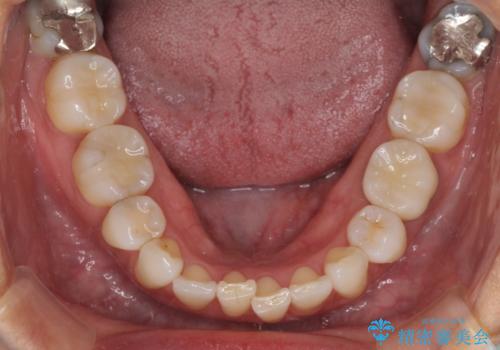

話をする度に相手の視線が銀歯に注がれている気がしているとのことでしたが、目立つ銀歯を自然な色合いに仕上げることができ、患者様には大変満足していただきました。